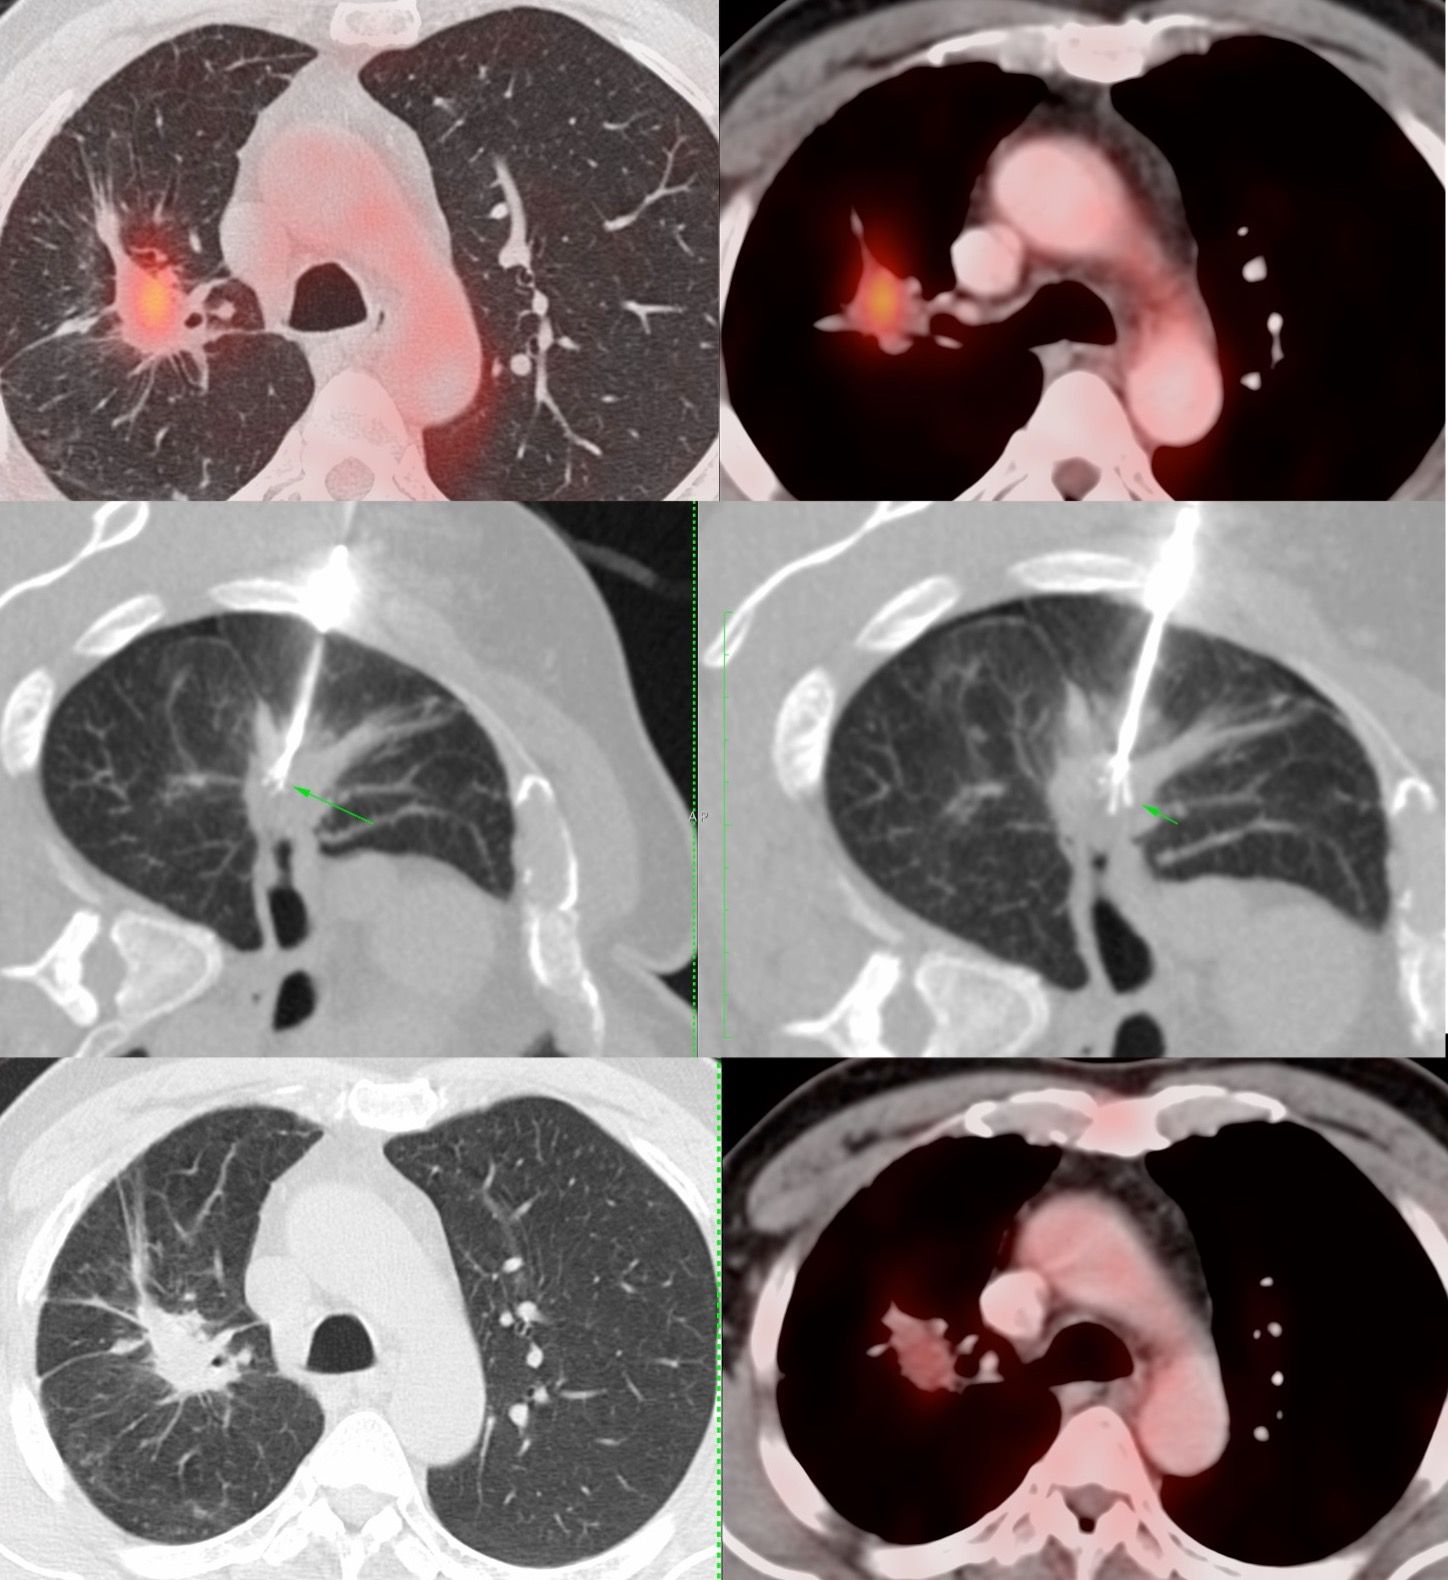

Case 41: Radiofrequency Ablation (RFA) of a Peri-Hilar Lung Mass

Bhavin Jankharia - 15 June 2021